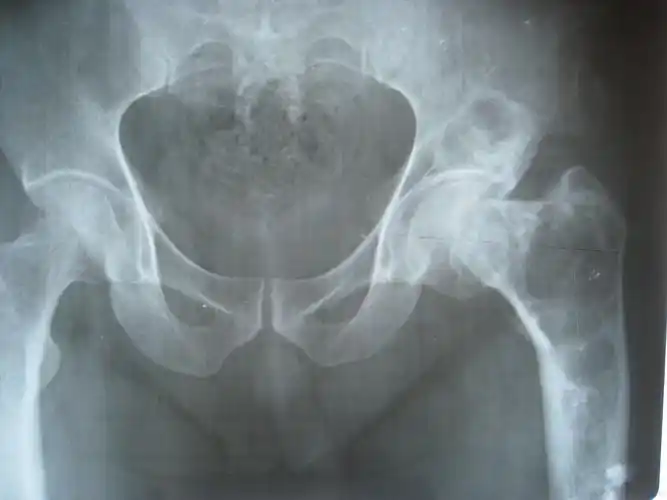

股骨近端站位骨囊肿

股骨颈骨囊肿极其严重 治疗方案 患者,女,57岁

【读片】我们新手互相学习,股骨上端囊性占位的鉴别诊断,附x光及ct片